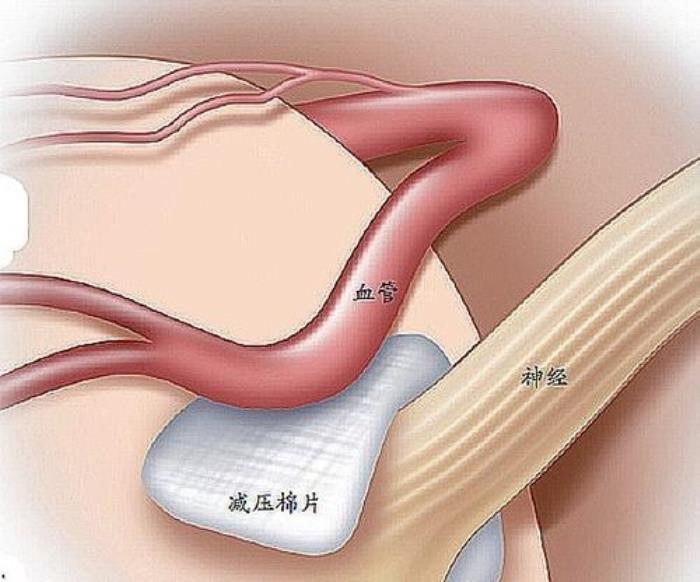

我们的大脑分布有许许多多的神经和血管,正常情况下,血管和神经是分开的,互不侵犯,各司其职。然而由于血管发育的差异,有些血管的走行就不那么规矩,而是扭曲不规则的。这就加大了压迫周围神经的可能。

面神经周围就有许多大血管,主要有小脑前下动脉、小脑后下动脉、小脑上动脉、椎动脉、迷路动脉等。这些动脉压迫面神经,而长期病理性刺激将导致面神经髓鞘变形、脱髓鞘。神经髓鞘是包裹在神经表面的一层保护膜,就好比电线的外皮,里面的铜线就是神经纤维,外皮长期受到压迫磨损暴露里面的铜线。而我们的面神经是由许许多多的神经纤维组成的,神经纤维外皮磨损了就会造成短路,从而引起面神经痉挛的发生。

手术主要是切除肿瘤,用特殊医用棉片隔离血管和神经,及对蛛网膜进行充分松解,避免牵拉神经。